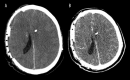

BACKGROUND Decompressive craniectomy is a common life-saving intervention in the setting of elevated intracranial pressure. Cranioplasty restores the calvarium and intracranial physiology once swelling recedes. Cranioplasty is often thought of as a low-risk intervention. However, numerous reports indicate that malignant cerebral edema (MCE) is an often-fatal complication of an otherwise uneventful cranioplasty. A careful review of the literature is needed to better understand this devastating condition. CASE REPORT A 41-year-old man presented after suffering a gunshot wound to the right frontal lobe. Upon initial evaluation, the patient had grossly visible brain matter, left-sided hemiparesis with a Glascow Coma Score (GCS) of 11, and vital signs concerning for elevated intracranial pressure. Computed tomography (CT) showed right-sided intraparenchymal and subarachnoid hemorrhage with a 5 mm leftward midline shift. The patient was taken to the operating room (OR) for right fronto-parietal craniectomy. Over the next 3 months, he recovered steadily and underwent PEEK cranioplasty on post-operative day 83. Pre-operative CT showed sunken skin flap syndrome with an 8-mm midline shift. Following an uneventful cranioplasty, he failed to regain consciousness. Examination revealed absent brainstem reflexes. CT showed global diffuse cerebral edema. The patient was declared brain dead. CONCLUSIONS Continued research is needed to better understand the pathophysiology of malignant cerebral edema so that future incidences may be prevented. A combination of negative-pressure suction drainage, sunken skin flap syndrome, and delayed time to cranioplasty likely play a significant role in the evolution of MCE. We urge neurosurgeons to consider the likelihood of MCE and adapt surgical planning accordingly.